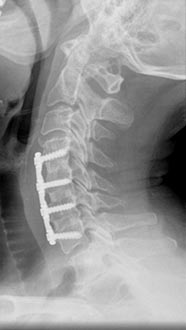

70 year old presented with spinal cord injury and quadriplegia after a fall.

Patient underwent laminectomy and fusion with complete resolution of the weakness and numbness.